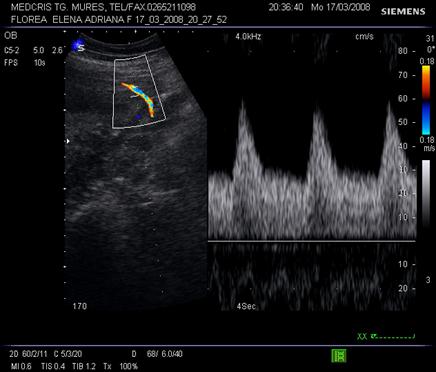

Doppler venos

Vena ombilicala - fluxul vascular poate fi apreciat in cordonul ombilical sau in abdomenul fetal. De obicei spectrul este monofazic daca fatul este in repaus motor si respirator.

Aspecte patologice ale spectrului Doppler constau in pulsatii venoase. Acestea par fiziologice, in timpul miscarilor respiratorii, iar patologice in trim. II si III in anomalii cardiace, aritmii sau insuficiente cardiace. Daca sunt asociate cu absenta fluxului end - diastolic in artera ombilicala, e vorba de insuficienta placentara si mortalitate de 50 - 60% [10,12].

Fig. nr. 327. Doppler cu pulsatii in vena ombilicala, in RCIU marcat la 34 sapt.